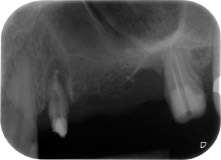

Nous avons toutefois maintenu notre projet initial de conservation des deux dents comme piliers temporaires d'un bridge pendant la période de six mois nécessaire à l'ostéointégration des implants. À la prochaine incision, la situation devrait être réétudiée. Premièrement, afin de gérer le problème endoparodontal, la surface de racine restante a été soigneusement débridée à l'aide d'un équipement piézoélectrique (Piezomed, W&H, utilisé avec l'insert en forme de spatule S1, initialement conçu pour limer la paroi sinusienne latérale) (Fig. 4).

Puis l'apex a été limé à l'aide du même instrument afin d'éliminer les tissus apicaux infectés résiduels et de réduire les éventuelles ramifications des canaux radiculaires (apicectomie) (Fig. 5). Il n'a pas été nécessaire de procéder à une obturation rétrograde car l'obturation orthograde venait juste d'être reprise.